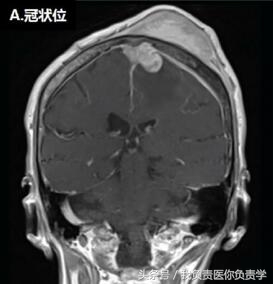

脑MRI显示,患者左侧额-顶部有一较大占位,增强扫描可见强化,从颅内、外延伸至上矢状窦(如图下所示),累及左侧额叶、顶叶和颞骨,左侧硬脑膜增厚。在颅内肿块压迫下,临近部位脑组织表现出血管性水肿。

▲头皮下占位病变。上图可见一较大的颅内外占位性病变,延伸至上矢状窦、大脑、软组织和颅骨。图(A)和图(B)T1增强见左侧硬脑膜增厚;图(C)T1可见脑水肿,图(D)为T2。